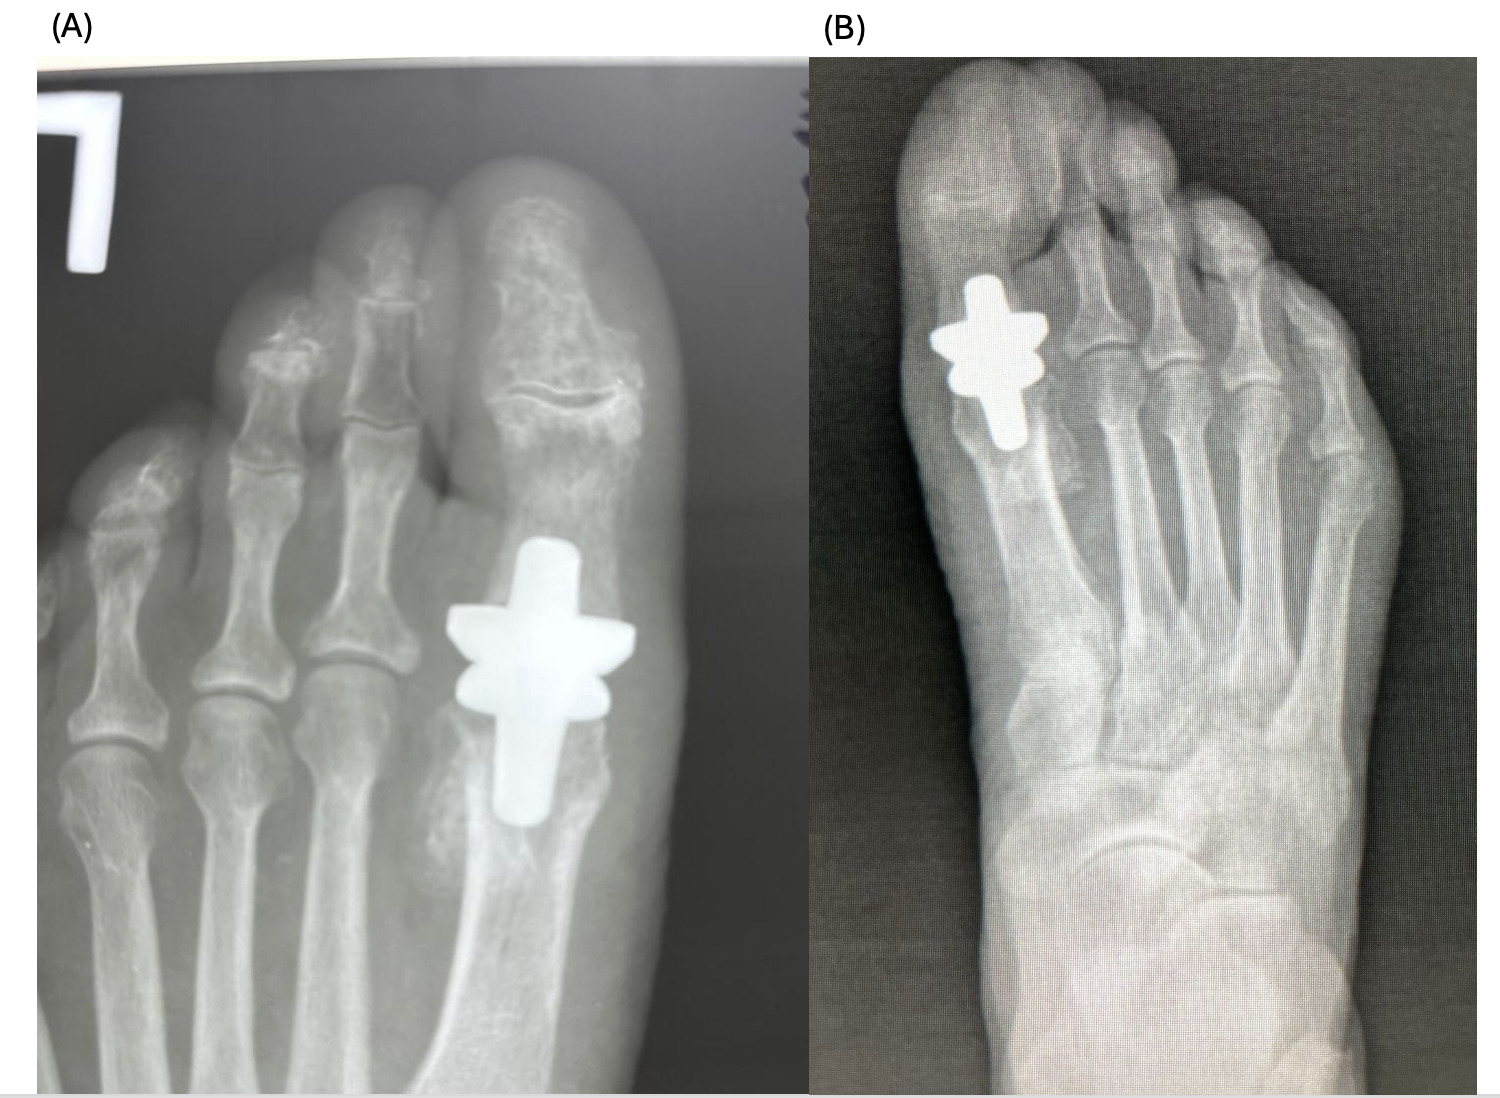

._patient_c__immediate_postoperative_radiograph_(b).png)

._patient_c__6-month_follow-up_radiograph_(b).png)